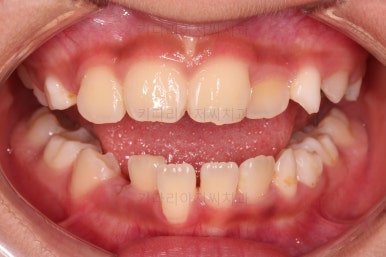

무려 4개월 만에 부산어린이교정 치료가 종료되었습니다.

앞니의 교합이 매우 안정적이여서 치료를 끝냈고요.

전후 비교해 보겠습니다.

반대교합이 완벽히 개선되면서 주걱턱으로 보였던 얼굴형태도 완벽히 개선되었고요.

한 쪽으로 치우치던 아래턱의 위치도 돌아오면서 비대칭이 개선되었습니다.

심지어는 위아래 앞니가 삐뚤었던 부분도 일정 부분 좋아졌습니다.